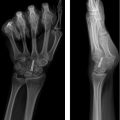

Obtain high-quality radiographs of hand: three views (Postero-anterior, lateral, oblique)

Obtain films of contralateral hand to serve as a template for baseline normal anatomy

Obtain films of initial injury whenever possible

Pathoanatomy of Malunion

Identify the site and direction (rotational, angular, shortening) of the malunion